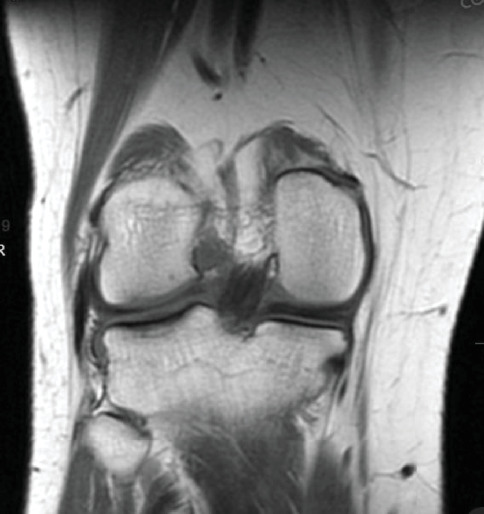

Purpose: Our work describes the use of matrix-induced autologous chondrocyte implantation (MACI) for a lateral tibial plateau osteochondral defect, in the setting of a concomitant meniscus repair and anterior cruciate ligament (ACL) reconstruction. To our knowledge, there is minimal research describing the application of MACI for cartilage defects of the tibial plateau, which brings about its own challenges. Methods: A 26-year-old male presented with lateral right knee pain and instability following a soccer injury. A bucket-handle lateral meniscus tear, 2 cm by 2 cm osteochondral defect of the lateral tibial plateau, and complete ACL tear were identified on magnetic resonance imaging (MRI). Our case vignette describes a two-stage MACI procedure for an osteochondral defect of the lateral tibial plateau with concurrent all-inside meniscus repair and ACL reconstruction using bone-patellar tendon-bone (BTB) autograft. Results: Follow up period was 20 months with excellent patient satisfaction and resolution of pain. Outcome measures (International Knee Documentation Committee (IKDC)) and Knee Injury and Osteoarthritis Outcome Score (KOOS) returned to preinjury levels at 8.5 months. Return to sport was achieved at 10 months postoperatively. Conclusion: The miniopen MACI procedure provides a logistically reasonable technique mitigating the anatomic challenges of tibial plateau osteochondral defects and potentially providing improved long-term outcomes. It is our hope that this work will contribute to the current understanding of the treatment options for osteochondral defects of the tibial plateau.

Abstract Image